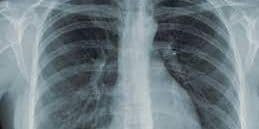

स्वास्थ्य विभाग के आंकड़े के अनुसार, जिले में जनवरी से जुलाई माह तक 1367 टीबी मरीजों की पहचान की गयी है. इसमें 20 मरीज एमडीआर टीबी से ग्रसीत हैं, जाे गंभीर स्थिति में हैं. इनका इलाज स्वास्थ्य विभाग की ओर से किया जा रहा है. दो सितंबर से एक नवंबर तक विशेष अभियान चला कर टीबी मरीजों की तलाश की जानी है.

टीबी से चार प्रतिशत है मृत्यु दर

स्वास्थ्य विभाग के अनुसार, 2020 में 1348 मरीजों की पहचान की गयी थी. इनमें 51 टीबी मरीजों की मौत भी हो गयी है. यह दर करीब चार प्रतिशत है. निक्षय पोषण योजना के तहत मरीजों को प्रत्येक माह राशि नहीं मिली, तो आंकड़ा बढ़ भी सकता है.